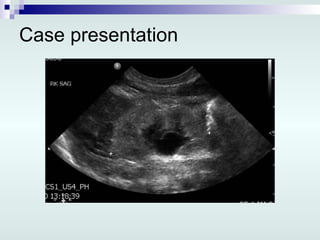

Case presentation In HSC, 3 rd  day of life: Repeated US: Lt multicystic dysplastic kidney, 6.4 cm Rt kidney smallish, 3.5 cm,  ↑ echogenicity, poor corticomedullary differentiation, mild pelvic dilatation Urinary bladder is minimally distended Minimal intraperitoneal fluid

Case presentation InHSC, 3 rd day of life: Repeated US: Lt multicystic dysplastic kidney, 6.4 cm Rt kidney smallish, 3.5 cm, ↑ echogenicity, poor corticomedullary differentiation, mild pelvic dilatation Urinary bladder is minimally distended Minimal intraperitoneal fluid